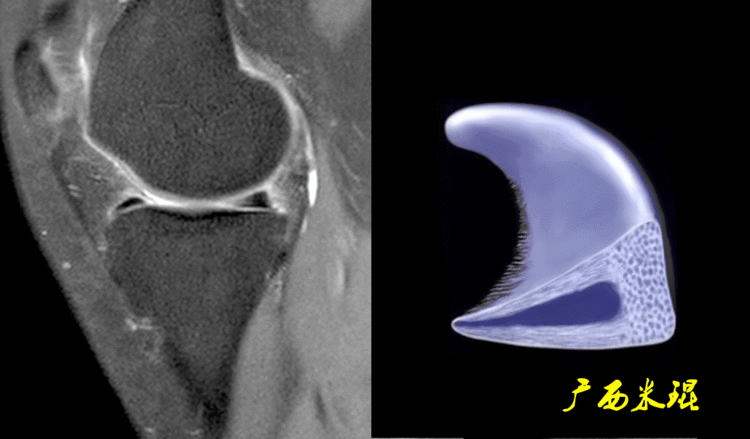

7、半月板后角内侧半月板周径较大,形似“C”形,后角宽,前角窄,后角宽度几乎是前角的2倍;外侧半月板周径小而面积大,形似“O”形,中部宽阔,前后角匀称,而且内外侧半月板后角为了适应内外侧胫骨髁和股骨髁而有着不完全相同的形态。

(1)假桶柄MR冠状位上偏后的层面,“C”形或“O”形的内外侧半月板偏后侧层面有可能同时扫描到半月板体部和后角,容易误诊为桶柄状撕裂,而矢状位或横断位上半月板形态是正常的。

下面这张MR冠状位显示为内侧半月板后角的假桶柄,其母体(图片中内侧的那一部分半月板)并没有变小、形态及信号均正常。

下面这张MR冠状位显示为外侧半月板后角的假桶柄,尽管在髁间窝发现半月板信号,但其母体(图片中外侧的那一部分半月板)并没有变小、形态及信号均正常。

下面这张MR矢状位显示为类似双后交叉征,后交叉韧带前下方的低信号其实是正常的外侧半月板后角,半月板桶柄状撕裂多发生于内侧,绝大多数是前交叉韧带损伤的合并伤,此病人的前交叉韧带正常,通过其他截面的半月板阅片就能排除。